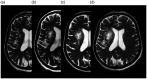

Cavernous malformations are angiographically occult vascular malformations. They are often associated with a developmental venous anomaly through poorly understood mechanisms. We present an unusual case of a gradually enlarging cavernous malformation associated with a developmental venous anomaly with arteriovenous shunting, suggesting venous hypertension or reflux as a potential cause of progressive growth.